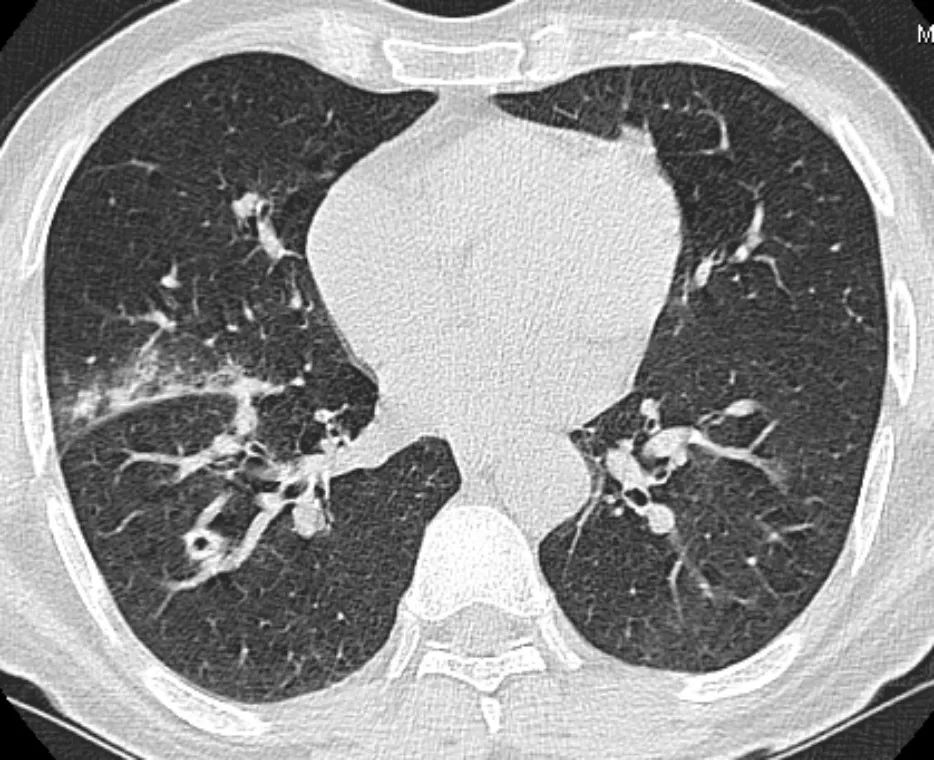

双肺多发空洞

诡异的双肺多发空洞1例

肺部空洞的鉴别诊断